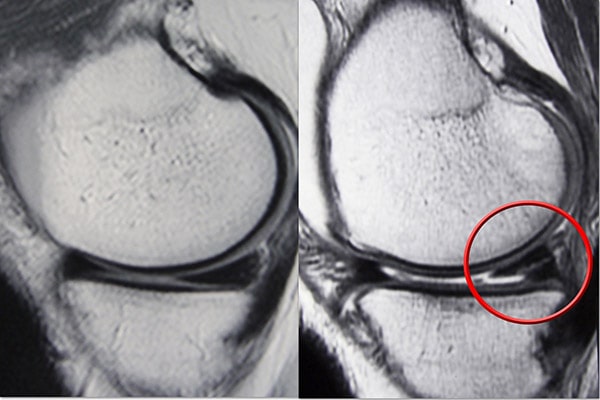

磁共振成像 (MRI) 掃描。 MRI 掃描可評估膝關節的軟組織,包括半月板、軟骨、肌腱和韌帶。

半月板外側三分之一的血供豐富。這個“紅色”區域的撕裂可能會自行愈合,或者通常可以通過手術修復。縱向撕裂是這種撕裂的一個例子。

相比之下,半月板內部三分之二的血液供應不足。沒有血液的養分,這個血流受限的“白色”區域的眼淚就無法愈合。由于碎片不能重新長在一起,因此通常通過手術修剪該區域對保守治療無反應的癥狀性撕裂。